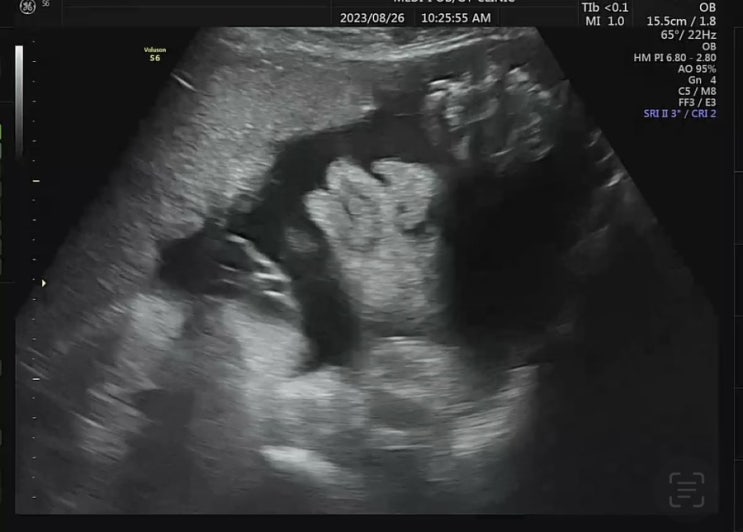

정상 정자 1% 미만, 자연 임신 성공

어느덧 임신한 지도 막달에 이르렀다. 혹시나 건강하지 못한 정자가 수정되어서 유산이 되는 건 아닐까 하...

임신 35주차 일상, 가족과 함께하는 시간 늘리기

35주차 증상 - 오른쪽 골반 통증이 꽤 오래 가기 시작 - 태동의 움직임이 느려짐. 꿀~렁 혼자 있었던 금요...

임신 33-34주차 일상, 드디어 휴직 시작!

33주차 증상 - 겨드랑이에 멍울이 잡힘(유방 초음파 검사 예정) 올 초까지 일했던 필테 센터 원장님을 만나...

임신 32주차 일상, 임신 9개월 진입!

#임신9개월 진입! #32주차 증상 - 눈이 침침해졌으나 핸드폰을 너무 많이 봐서 그런듯.. 전날 저녁, 급매로...